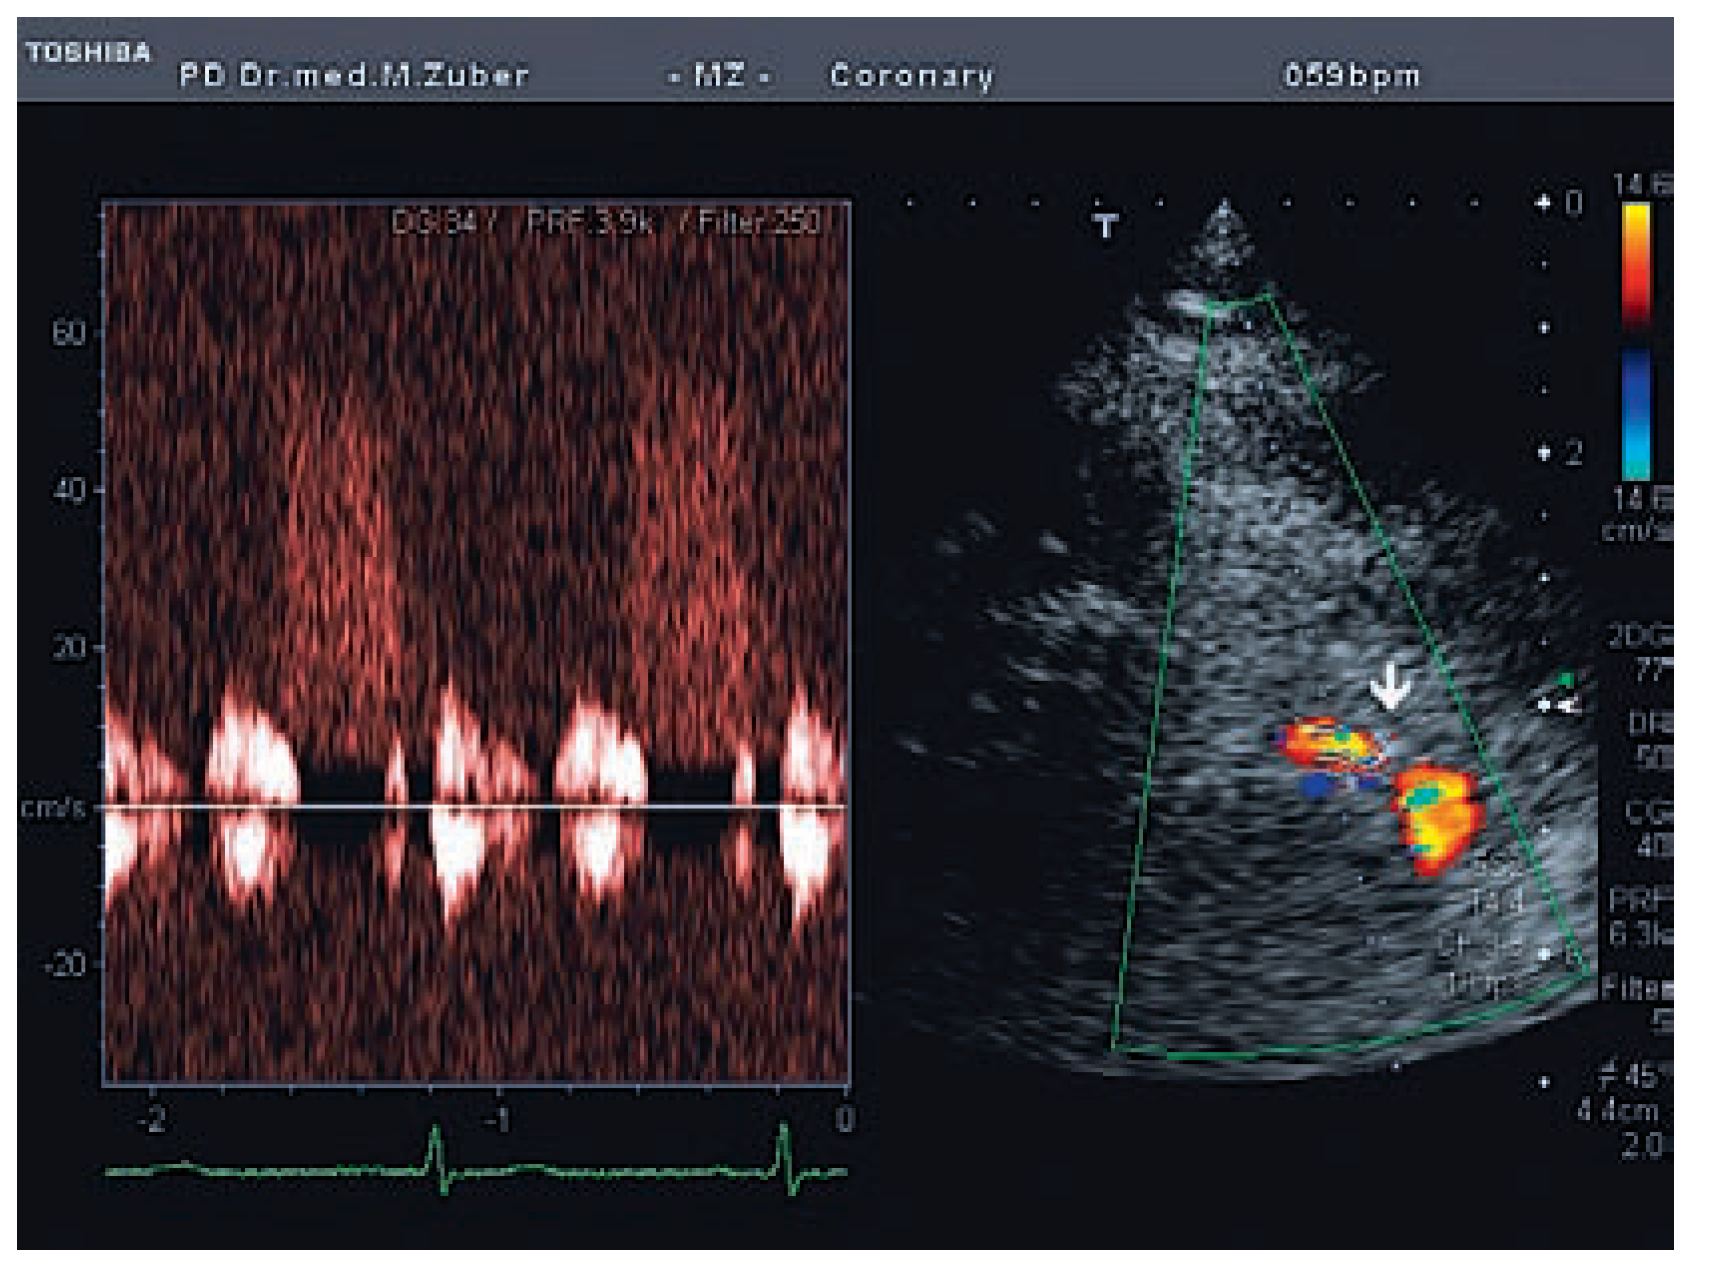

Koronarstenose Und Transthorakale Farbdopplerechokardiographie

Fallbeschreibung